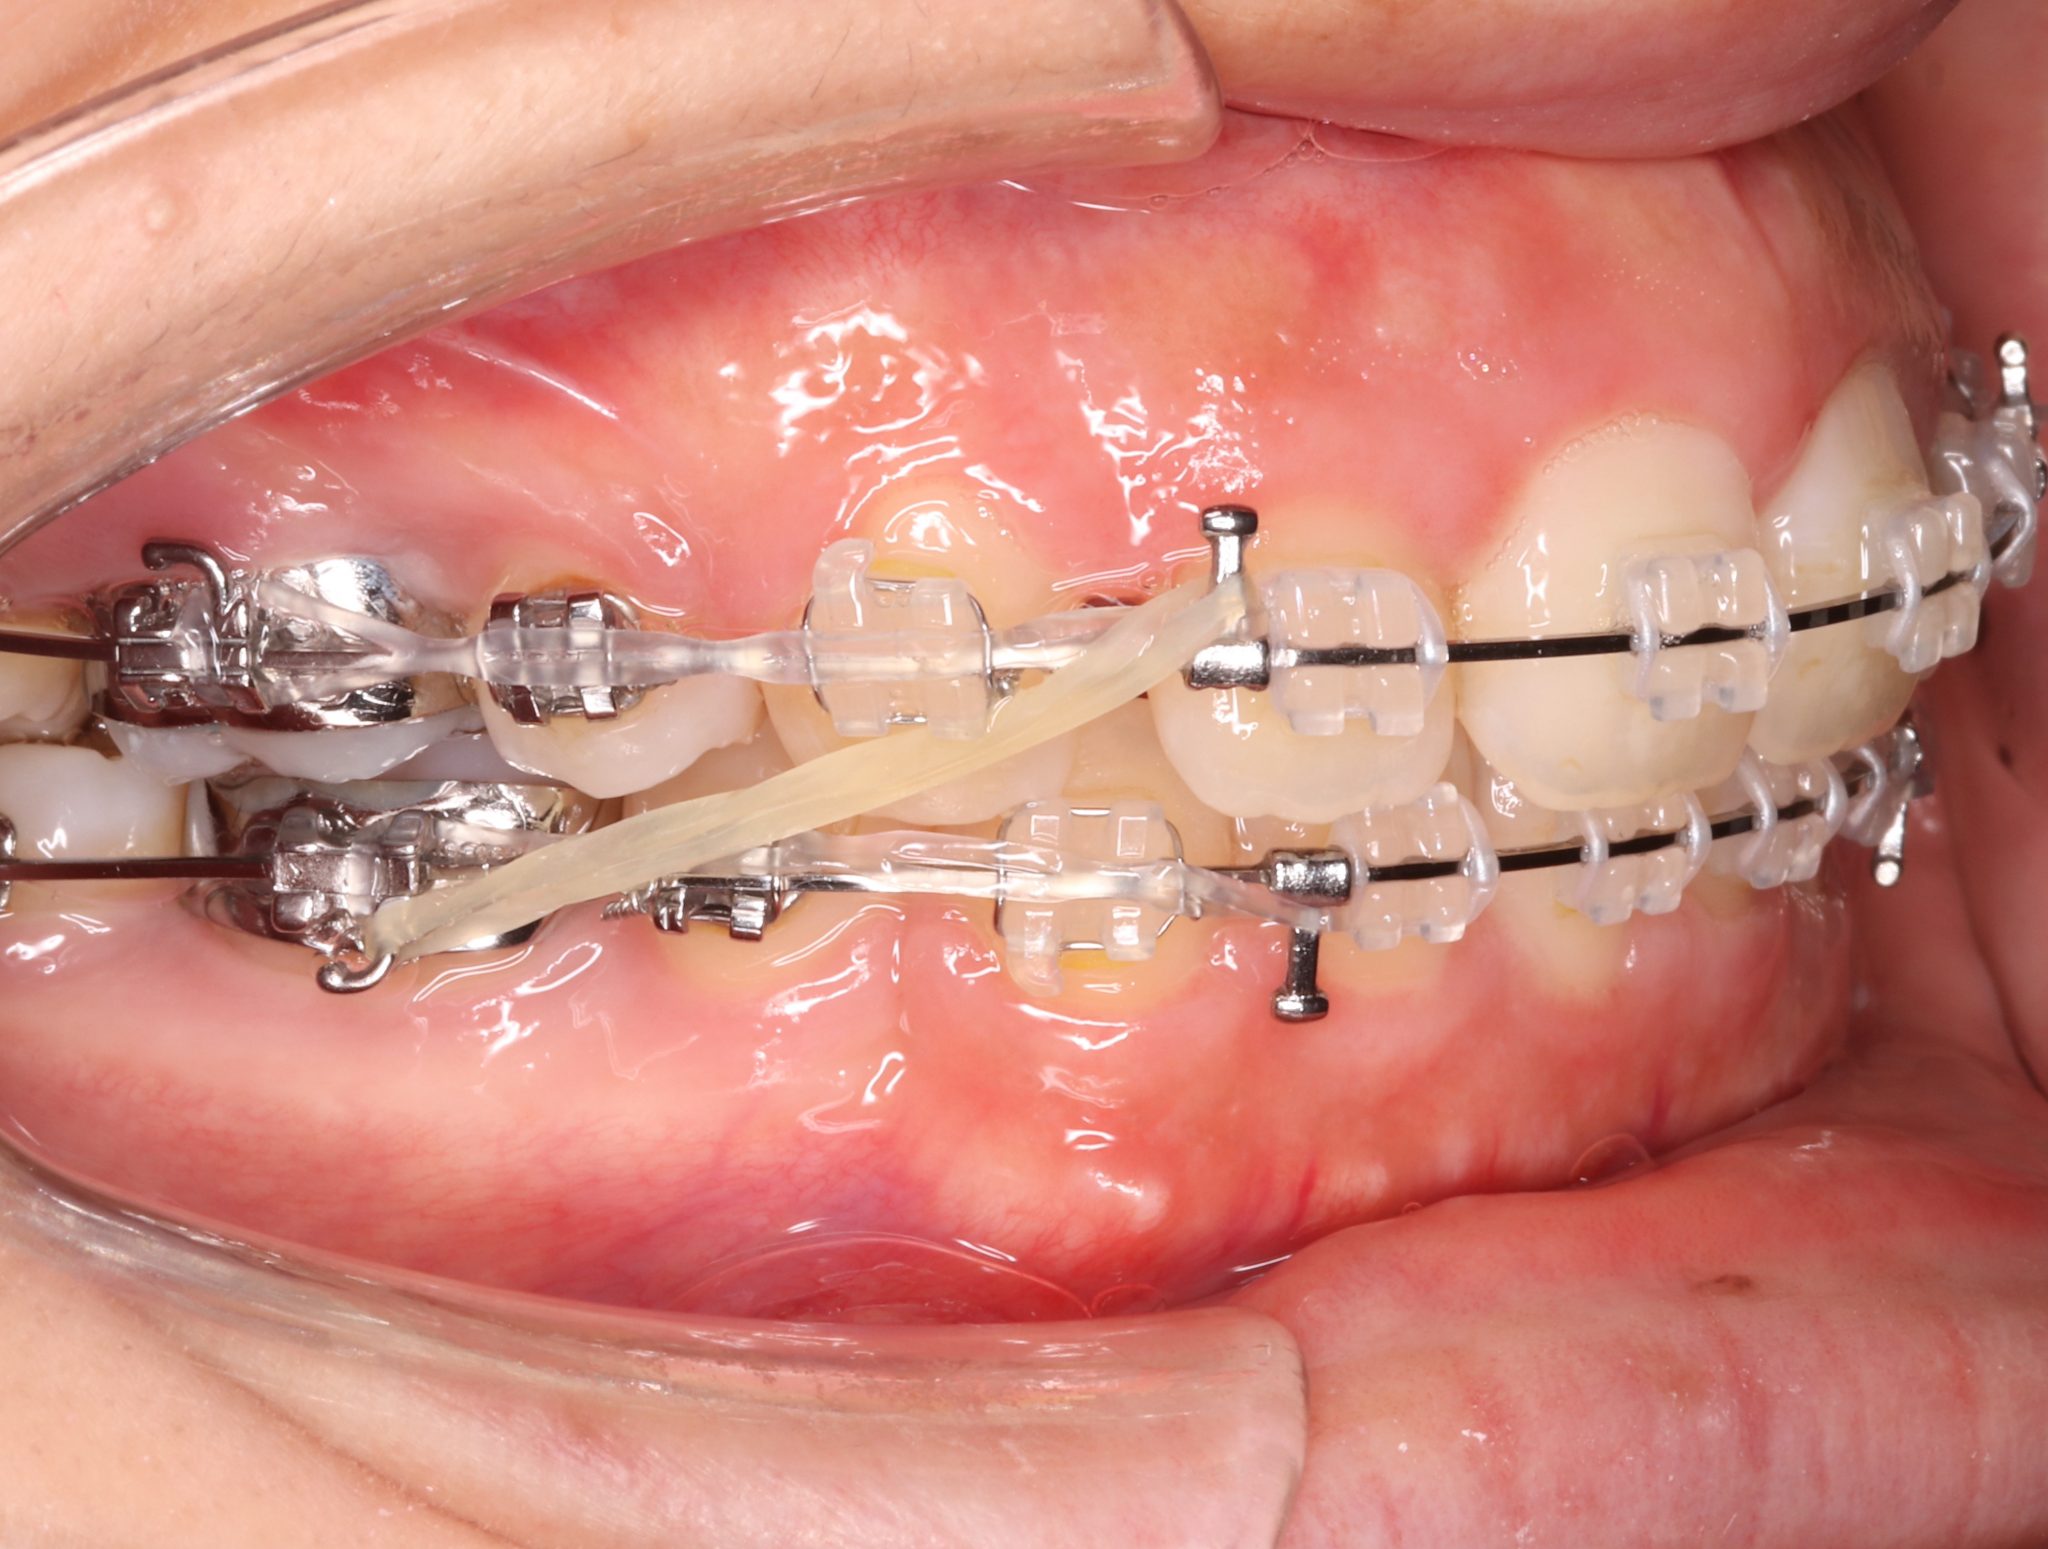

ゴムかけとは

歯列矯正治療を行う際に矯正装置(マウスピースやワイヤーなど)に

ゴムをかけることで、矯正力の補助的な力を歯に加える方法です。

ゴムかけは歯を引っ張る時や噛み合わせを合わせていく時

などに行うことが多い処置内容です。

ゴムの牽引力により、

矯正装置だけではかけられない力を歯にかけることで

適切な噛み合わせを作ることが可能になります。